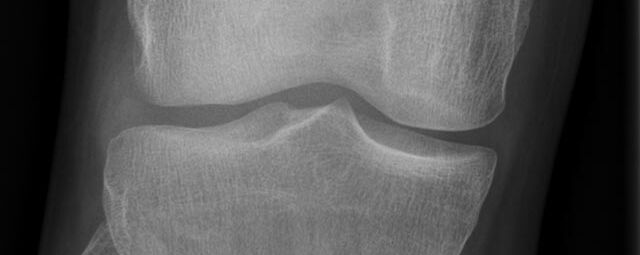

Röntgen Knochen

• Fraktur

• Arthrose

• Rheumatische Gelenkerkrankungen

• Degenerative Veränderungen der Wirbelsäule

• Knochentumor

• Osteoporose

• Therapiekontrolle nach OP am Skelettsystem

• Vollautomatische Erstellung von Ganzbein- und Ganzwirbelsäulenaufnahmen